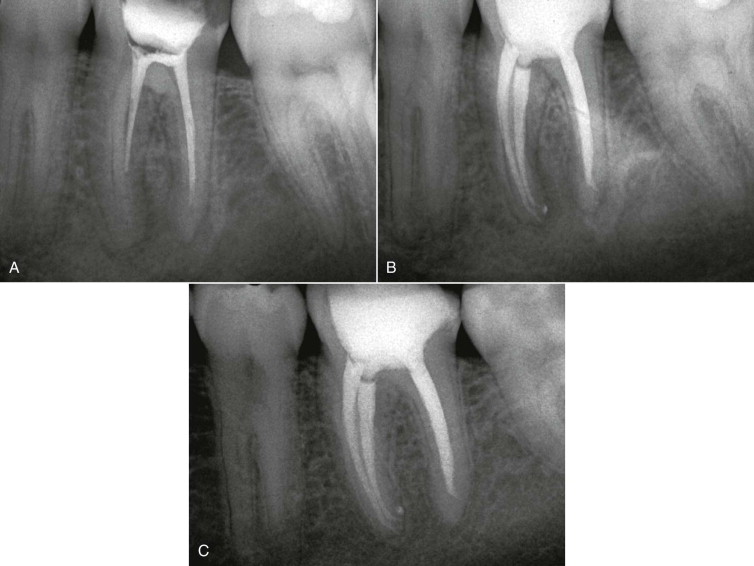

Is Root Canal Treatment painful at your clinic?

At Dr. Ritika's EndoElite Implant, Laser & Aesthetic Centre, Root Canal Treatment is performed using modern rotary instruments and digital imaging. The procedure is safe, comfortable, and almost painless under local anesthesia.